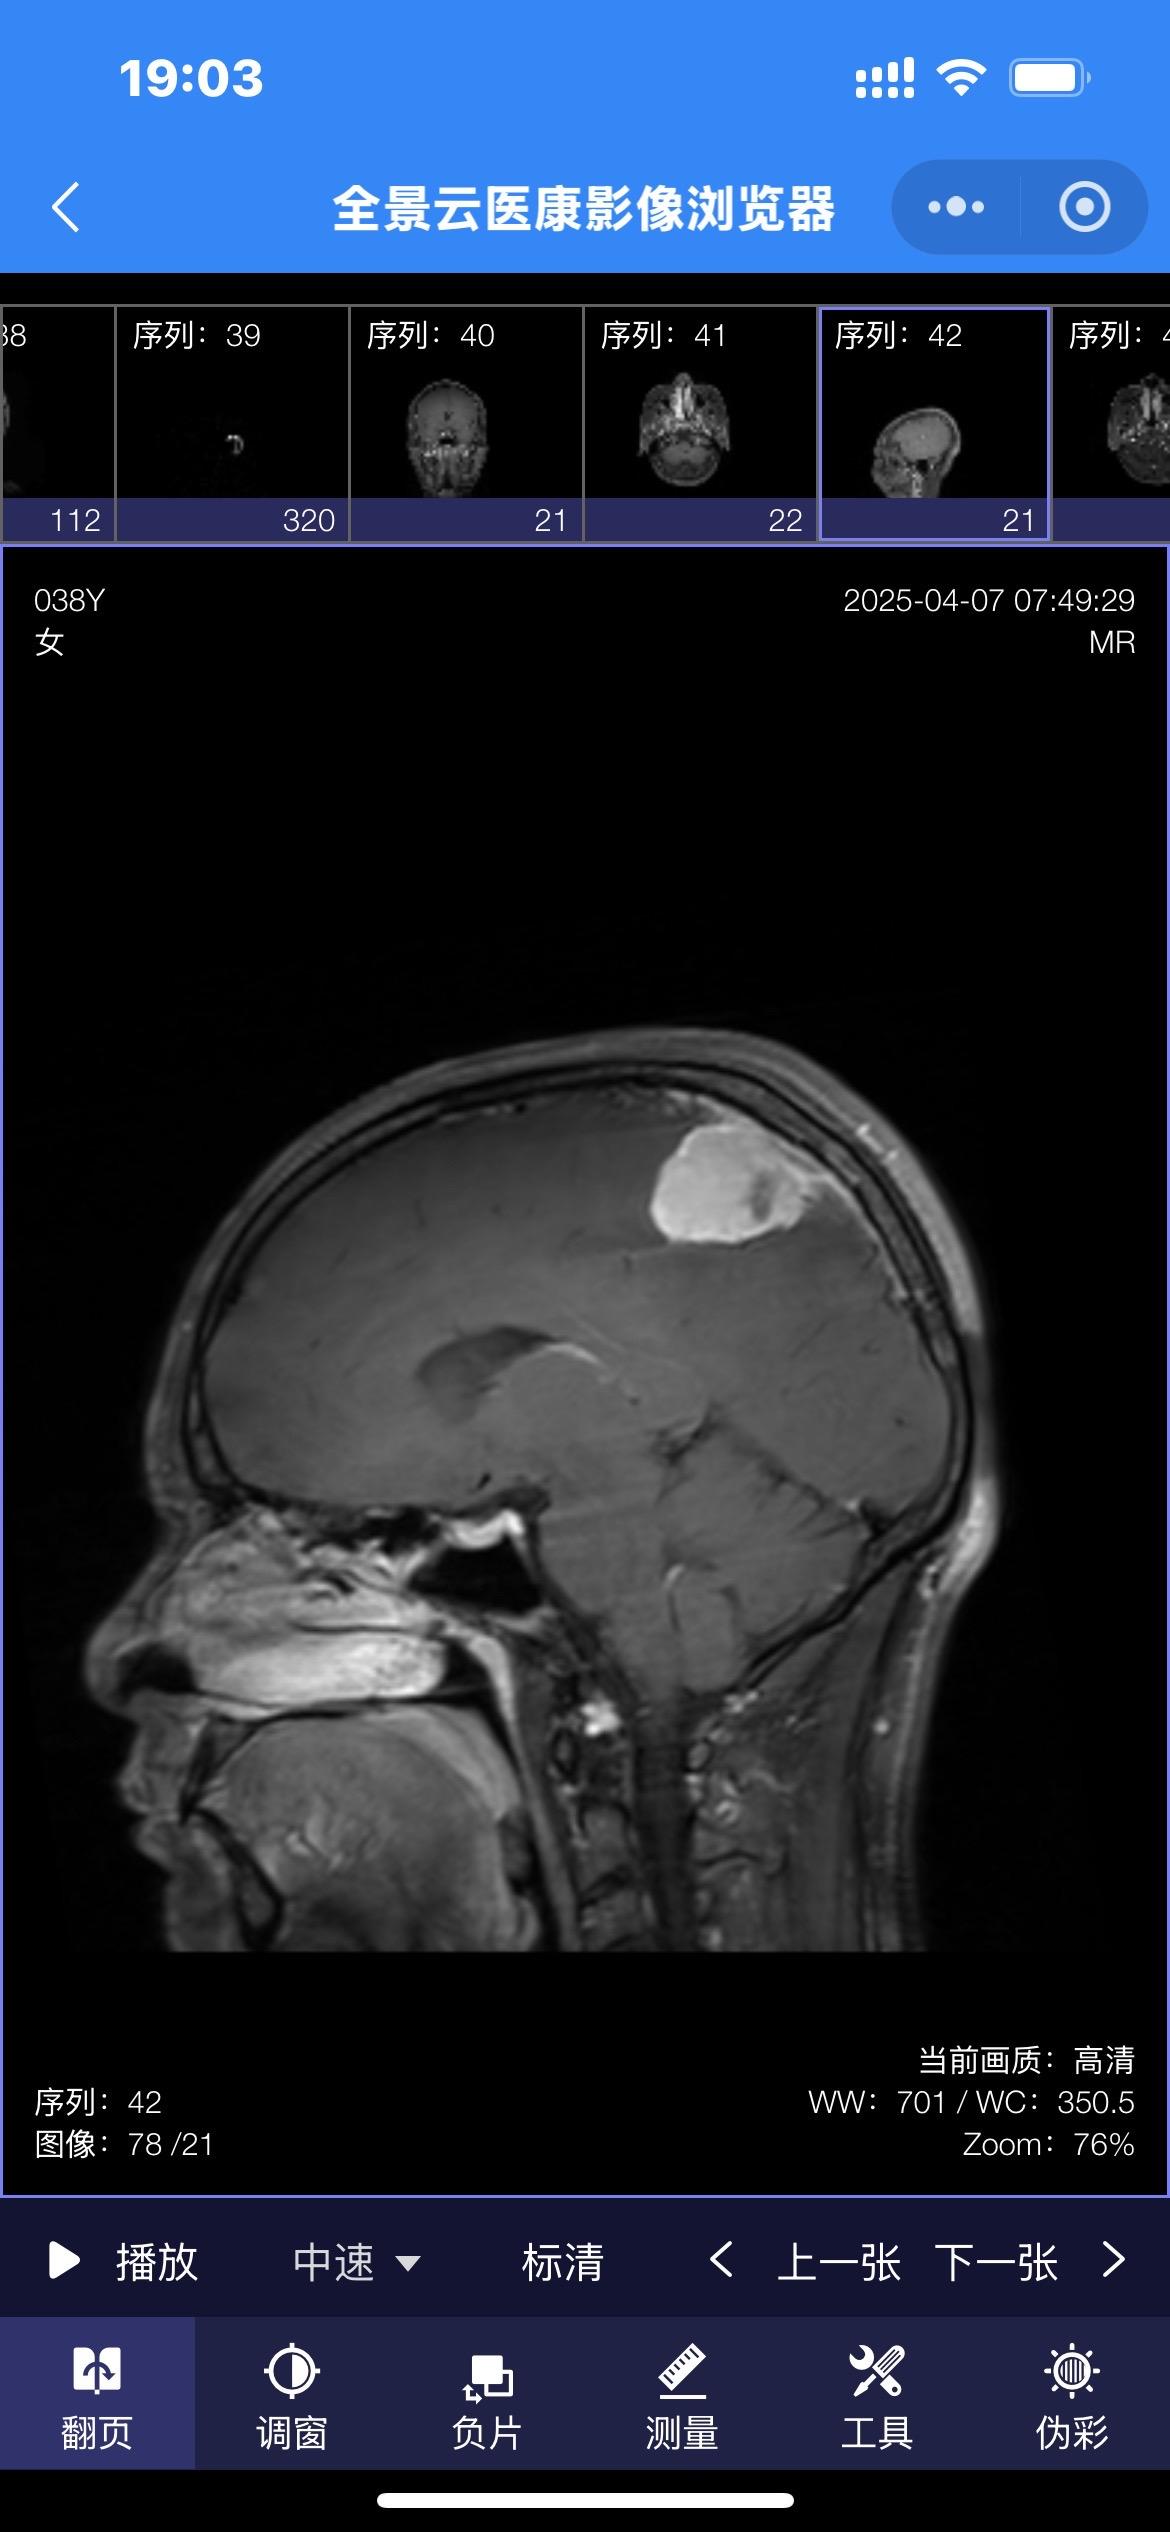

38岁女性因头痛发现脑膜瘤。脑膜瘤在女性的发病率要高于男性! 首选的治疗方法就是切除肿瘤。 有的脑膜瘤切除的难度不大,有的脑膜瘤却是难以切除干净的。 这个脑膜瘤位置就不太好,位于中央区(有重要的功能的区域),切除难度就很大!脑膜瘤手术